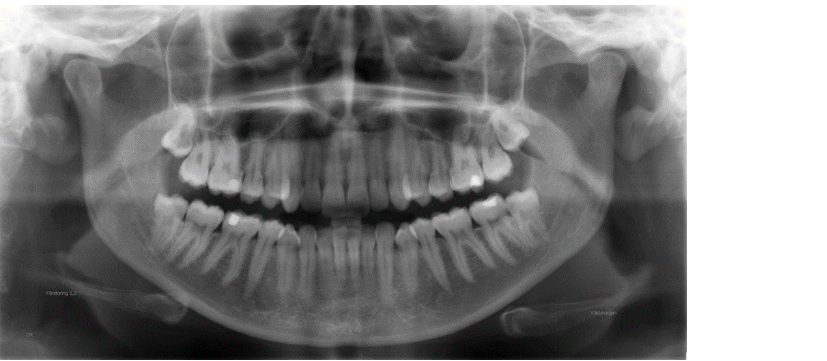

Bildexempel panoramabild

Icke-avbländad

Avbländad

Många gånger är man mest intresserad av tänderna och behöver inte avbilda hela käkarna. På de flesta panoramamaskiner finns möjligheten av avblända bilden och på så sätt reducera stråldosen. Här ovan ses ett dentalt panorama. Ofta finns också möjligheten att avbilda patientens ena sida.